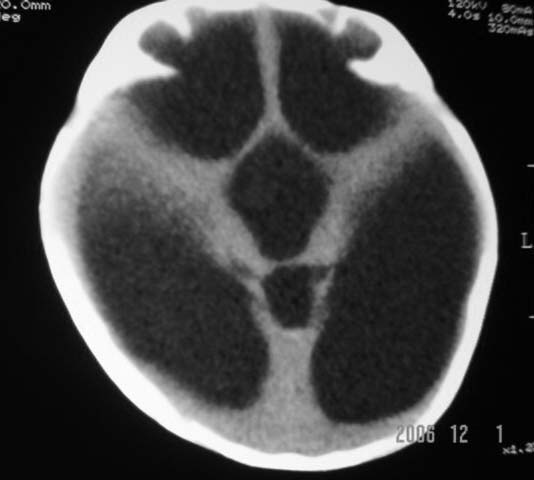

3m,出生时有新生儿吸入性肺炎、hie、化脓性脑膜炎,近一个月发现头围增大(51cm),无恶心呕吐。

第四脑室有增大,应该是交通性脑积水

3m,出生时有新生儿吸入性肺炎、hie、化脓性脑膜炎,近一个月发现头围增大(51cm),无恶心呕吐,脑室系统全程扩张,脑皮质变薄,结合病史考虑交通性脑积水

脑室全部扩大结合化脓性脑膜炎病史考虑重度交通性脑积水.

3m,出生时有新生儿吸入性肺炎、hie、化脓性脑膜炎,近一个月发现头围增大(51cm),无恶心呕吐,脑室系统全程扩张,脑皮质变薄,结合病史考虑重度交通性脑积水。